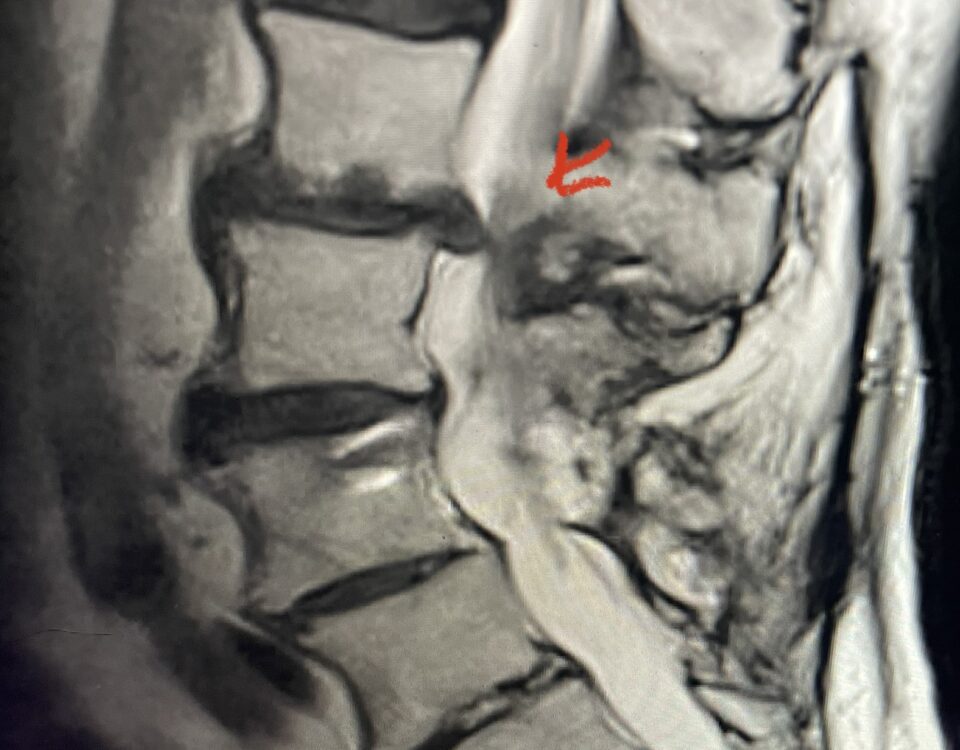

The actual structural cause of lumbar thecal sac compression can vary in degenerative spondylolisthesis and stenosis. The culprits are commonly thickened ligamentum flavum or severe facet […]